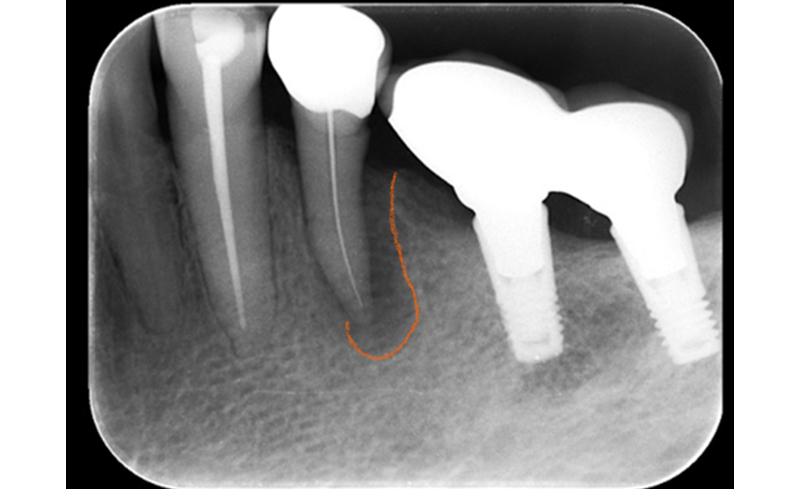

| 治療内容 | 初診時に右上の小臼歯部に骨の吸収が認められます(左図)。神経が死んでしまっていたので、根の治療を行ってから再生療法を行いました(右図)。点線部が再生された領域です(右図)。 |